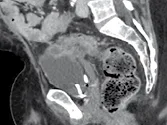

Figure 9. Métastases hépatiques d’un cancer du colon. Récidive après résection

chirurgicale traitée par association contenant du bévacizumab.

A. Examen initial et B, examen après quatre cures. En comparant ces deux coupes

acquises au temps portal après injection, on voit la quasi disparition

du rehaussement après traitement. Malgré l’absence de changement du grand

diamètre, c’est un signe de l’efficacité antio-angiogénique de la thérapie ciblée